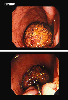

A case of colonic lipoma with intussusception and ulcers in the surrounding mucosa.

Endoscopy